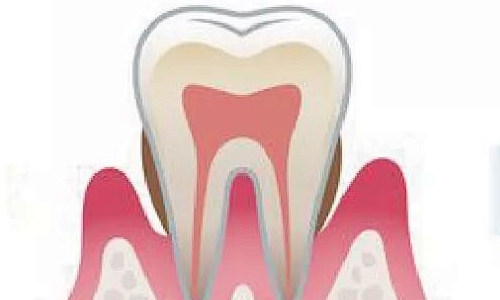

| 根管治疗(前牙) | 800-1200起 |

| 根管治疗(后牙) | 1000-1800起 |